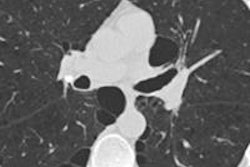

Of course, one issue with coronary calcium is the need for gated scans to stop cardiac motion; CT lung cancer screens are ungated.

Dr. Mathias Prokop, PhD, from Radboud University."But we all know that we see calcium on these [ungated] scans, and there is a good correlation between gated and ungated CT," he said. "There is a slight underestimation with ungated scans, but it doesn't mean there is always underestimation."

Some images will show more calcium than exists and some less, but generally the calcium that readers see on ungated scans is really there, Prokop said.